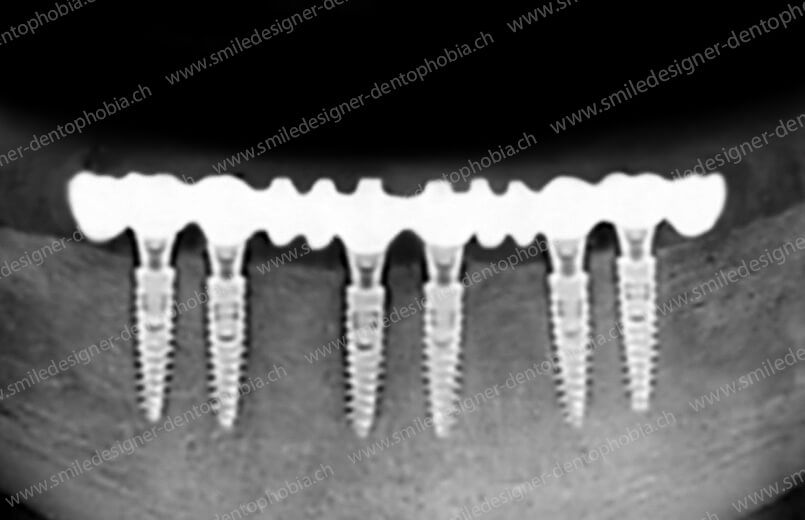

- Pose de 8 à 10 implants :

- Répartis de manière symétrique pour assurer une stabilité mécanique et une répartition homogène des forces masticatoires.

- Adaptés au gabarit du patient et à la quantité d’os disponible.

- Bridge résilient provisoire :

- Armature métallique rigide (titane ou chrome-cobalt) pour immobiliser les implants.

- Revêtement en composite résilient pour absorber les chocs et protéger la cicatrisation.

- Posé 4 à 10 jours après la chirurgie, il guide la cicatrisation et permet une mastication douce pendant 6 à 12 mois.